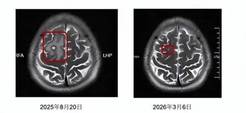

【单机】男子喝生猪血寄生虫钻入头部 医生:脑囊虫病

据九派新闻报道,近日,树兰(杭州)医院肝病暨感染科、浙江省医学会热带病与寄生虫病分会候任主任委员高海女主任医师诊室里,30多岁的小王拿着复查报告长舒一口气:颅内病灶较半年前明显缩小,身体抽搐症状消失。